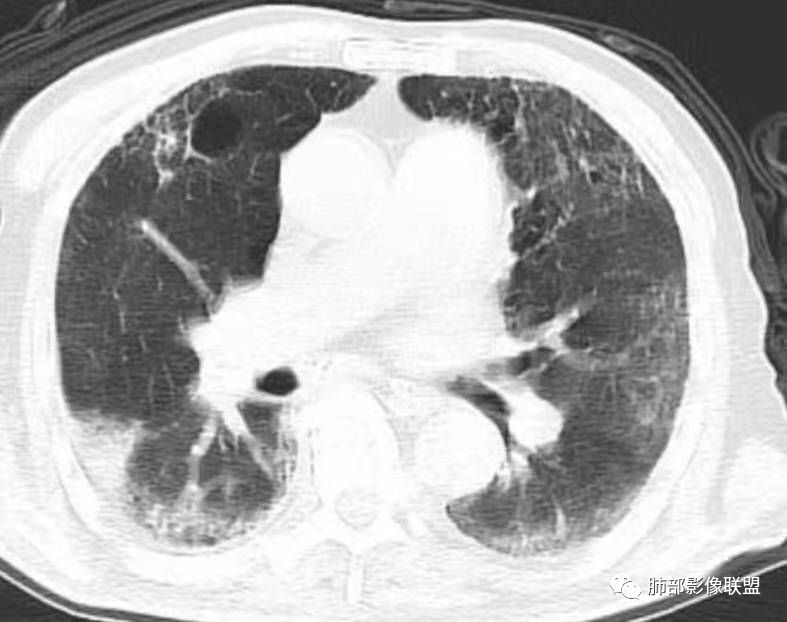

老年男性,糖尿病患者,右肺上叶大片状影伴多发小空洞和支气管充气征,有重力分布趋向,播散灶不明显,两肺胸膜下多发慢性炎症改变,有肺气肿肺大疱背景,肺门纵膈多发小淋巴结,少许钙化,急性起病,首先考虑感染性病变,1.气肿性肺炎?2.肺克?建议结合临床相关实验室检查,影像学角度常规治疗后复查除外粘液腺癌可能。右肺上叶一空洞内见结节影,考虑合并曲菌感染,干酪性肺炎可以,主要没有播散灶,结核待排吧

双肺多发GG0,外周分布,略受重力影响,部分可见囊,右上贴壁实变、气柱征、无璧空洞,卫星灶不明确,有2DM,常规考虑:间质肺基础,合并TB>坏死性肺炎(肺克)>腺癌。非常规:如HIV+,可能存在PCP并TB,似乎有曲菌球

尘缘:

老年男性,咳嗽气喘10天,双肺明显肺气肿,右上肺叶实变,内见大量空洞及囊腔样改变(部分为支气管扩张),实变区周围表现为网格样改变,有明显的小叶间隔增厚,边界似清非清,支气管走行僵硬,有枯树枝样改变,双下肺胸膜下小叶间隔增厚明显,边缘相对模糊,综合考虑如下:1、粘液腺癌可能大(枯树枝样改变,边界似清非清,小叶间隔增厚符合)。2、结核,右上肺似像干酷样改变,内有空洞及支扩样改变支持,但下肺及左肺无相关支气管播散的小叶中心结节及树芽,不支持,临床病症不支持,只有咳嗽,喘气,无咳痰及结核中毒症状。当然结核是妖,需要结合痰检及结核相关指标进一步明确。3、肺克,虽有10年糖尿病史,但肺部只有右肺改变明显,无胸膜下脓肿表现,无脓毒栓表现,临床症状也不支持。4、其他感染?双下肺胸膜下病灶边缘模糊,不完全除外,需要结合临床炎性指标分析。

一米阳光:

老年男性,右上肺大片实变,内见支气管充气征,支气管通畅,见多发蜂窝状改变,双肺肺气肿,双肺胸膜下间质性改变。结合病史,咳嗽,糖尿病史,考虑感染,结核可能。鉴别肺炎型肺癌,肺克;建议增强,支气管镜检查

6、结核灶周围磨玻璃少见,粘液腺癌磨玻璃影清楚。结核灶常有收缩,钙化,树丫等等。很重要,粘液腺癌分布弥漫,远处飘散的边界清楚的磨玻璃结节影有重要诊断意义。